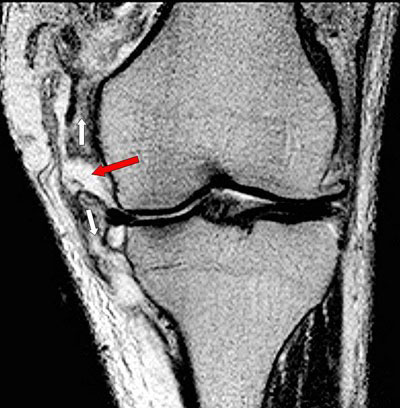

Op de foto is bij de rode pijl de scheur in de mediale band op een MRI van de knie goed te zien. De witte pijlen geven de richting van de kracht aan die bij een valgusexorotatie trauma tot een scheur leidt van de mediale band die op de foto ook verdikt is.

In dit geval werd gezien de complexiteit van het trauma gekozen voor een operatieve behandeling door de mediale band te hechten alvorens in een later stadium de voorste kruisband operatief te herstellen. Ook in geval van een avulsiefractuur van de aanhechting aan het bovenbeen (op de röntgenfoto meestal goed zichtbaar) wordt, indien het fragment is verplaatst, een operatieve behandeling gedaan en het geavulneerde fragment gefixeerd met een schroef of kram. Uitgestelde behandelingen van niet goed genezen mediale bandletsels zijn minder succesvol.